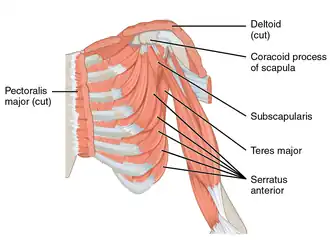

Коракоидный отросток (от греческого κόραξ — «ворон»[1]) — небольшой крючковидный вырост на боковом крае верхней передней части лопатки (отсюда лат. coracoid — «подобный клюву ворона»). Направленный вбок вперед, он вместе с акромионом служит для стабилизации плечевого сустава. Он пальпируется (прощупывается) в дельтовидно-грудной борозде между дельтовидной и большой грудной мышцами.

Восходящая часть, сплющенная в передне-заднем направлении, представляет спереди гладкую вогнутую поверхность, через которую проходит подлопаточная мышца (subscapularis).

Горизонтальная часть сплющена сверху вниз; его верхняя поверхность, выпуклая и нерегулярная, представляет собой место прикрепления малой грудной мышцы (pectoralis minor); нижняя поверхность гладкая; медиальные и боковые границы неровные; первая дает прикрепление малой грудной мышце, вторая — коракоакромиальной связке; вершина охватывается совместным сухожилием клювовидно-плечевой мышцы (coracobrachialis) и короткой головки двуглавой мышцы плеча и дает прикрепление ключично-грудной фасции.

Коракоидный отросток является местом прикрепления для нескольких мышц и сухожилий:

- Малая грудная мышца — к 3-му, 4-му, 5-му и в редких случаях 6-му ребру;

- Короткая головка двуглавой мышцы плеча — к бугру лучевой кости;

- Клювовидно-плечевая мышца — к медиальной части плечевой кости;